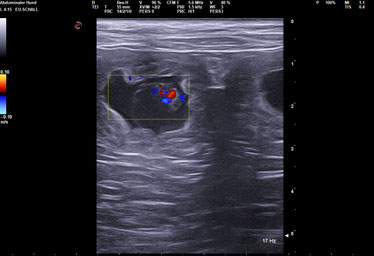

Da Wilma jetzt schon weit über der zu erwartenden Läufigkeit ist, habe ich sie bei einer Fach-Tierärztin in Dortmund "auf den Kopf stellen lassen". Es gibt keine organischen Gründe, alle Werte sind top. Alle Untersuchungen ergaben keinen negativen Befund. Und doch gibt es eine Erklärung von der Tierärztin:  Die veränderten Lebensumstände können durchaus einen Zyklus verändern, so wird es sein. Also warte ich jetzt geduldig und entspannt auf die Läufigkeit.